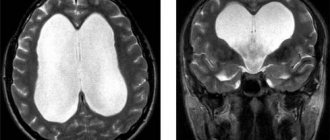

- Магнитно-резонансная томография. Более современная диагностика, дает более подробные и точные данные, за счет большей разрешающей способности аппарата и не так пагубно влияет на пациента.

Компьютерная томография – метод исследования, который позволяет увидеть точные и детальные малейшие изменения плотности мозговой ткани. К методам нейровизуализации относится магнитно-резонансная томография.